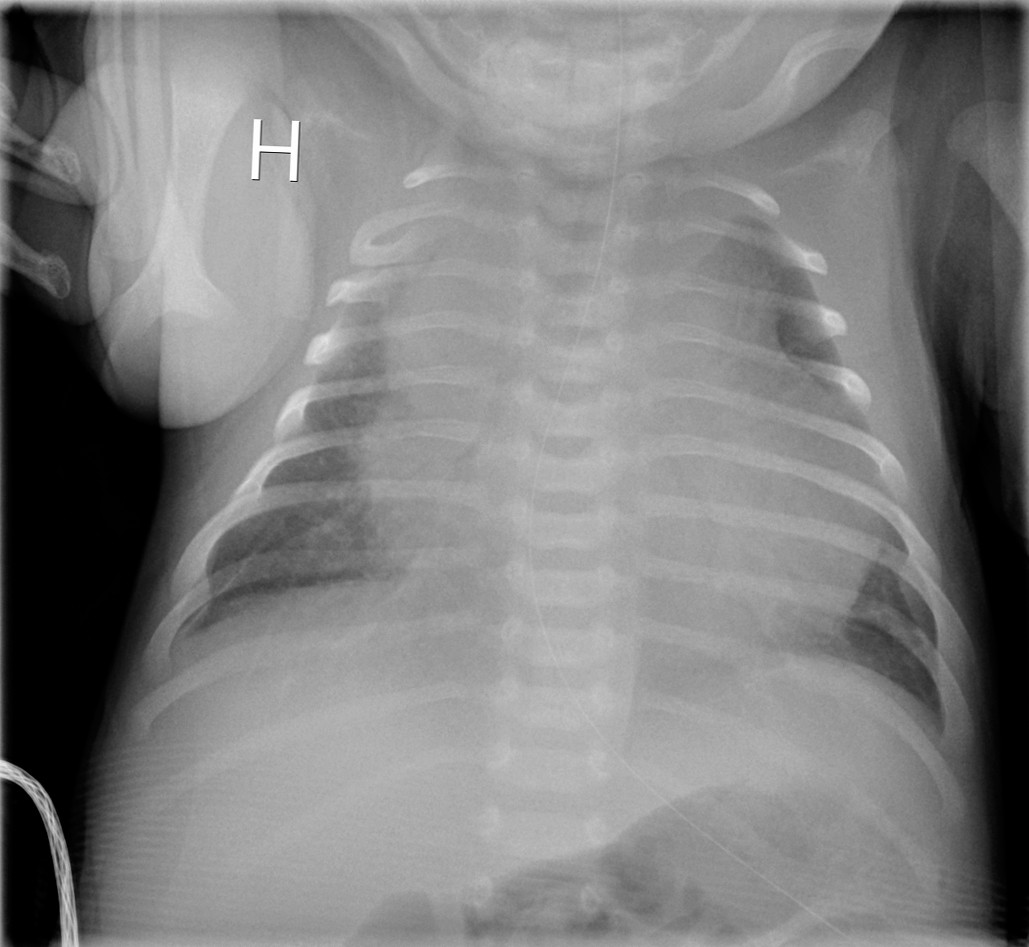

Dag 3 brukte barnet armene sidelikt, og allmenntilstanden var god. CRP steg til 170 mg/l og det vokste gule stafylokokker i blodkultur. Dag 6 ble det observert lett påskyndet respirasjon med normal SpO2. Røntgen thorax viste betydelig breddeforøket hjerteskygge (bilde 2). CRP var da 90 mg/l. Ekkokardiografi viste perikardvæske med preg av pretamponade. Han hadde imidlertid normalt middelblodtrykk på 60 mm Hg og normal hjertefrekvens på 150–160/min. Kapillærfylningstid ble ikke målt, men barnet var klinisk velsirkulert ved overflytning til regionssykehuset, hvor det ble utført ultralydveiledet tapping av perikardvæske. Det var oppvekst av gule stafylokokker i perikardvæsken.